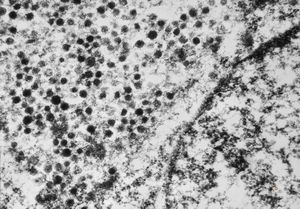

F, 24y. | molluscum contagiosum … virions